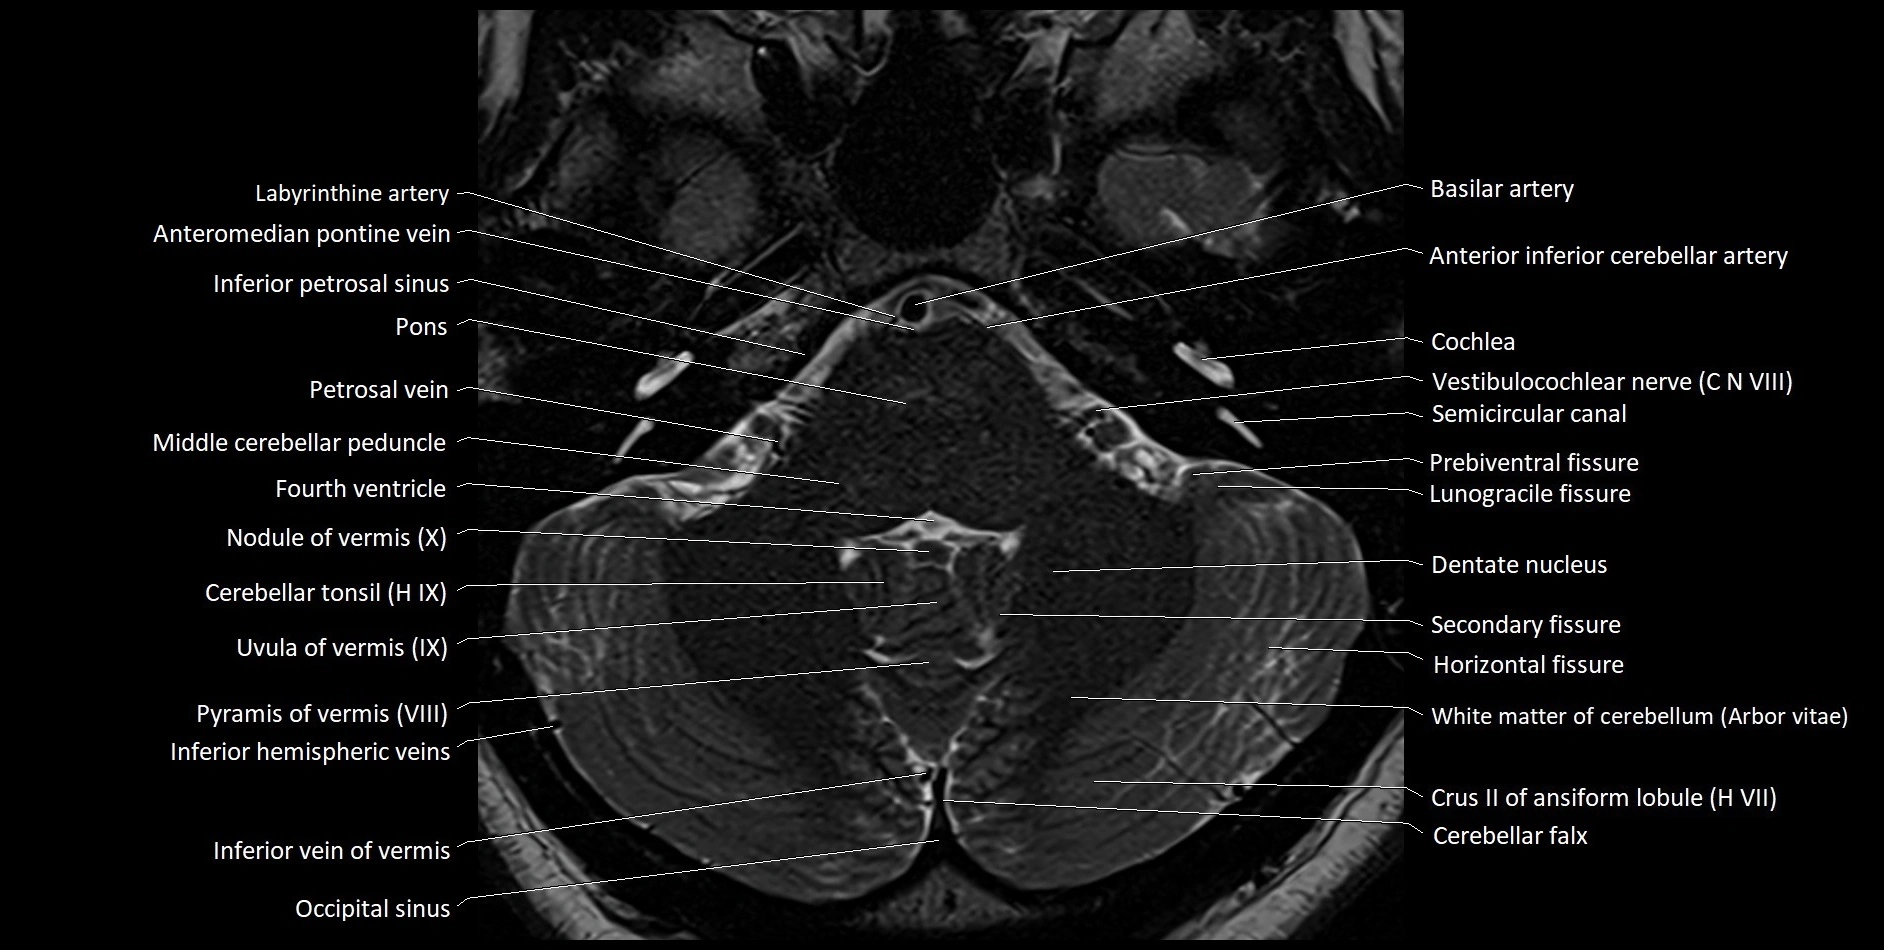

MRI images